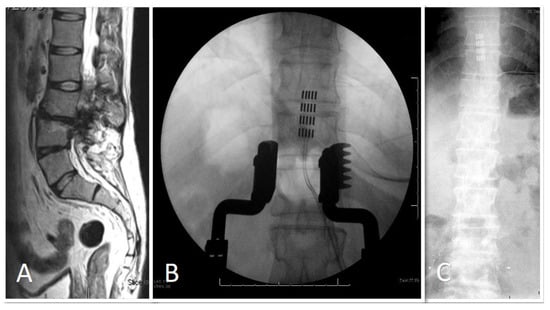

| 55 | M | Transverse myelitis | Percutaneous | Boston | FAST | T3 |

| 59 | M | Transverse Myelitis C2–C5 + FBSS L4/L5 | Percutaneous T8–9 | Nevro (Redwood City, CA, USA)  | HFX | T8 |

| 66 | M | T10 to L5 spinal fusion procedure | Paddle T7 to T10 | Nevro | C | HFX | Mid T9 |

| 65 | M | T8 SCI | Paddle over T2 | Abbott | A | Paraesthesia | Mid T2 |